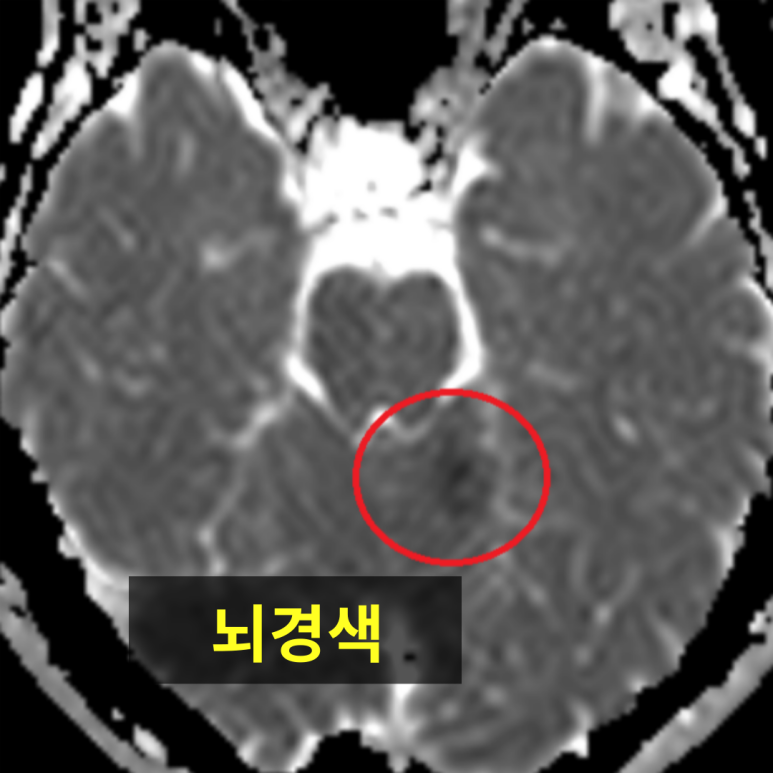

뇌CT 검사에서 발견되지 않는 뇌백질 변성

미세하게 발견된 뇌백질 변성(뇌노화의 척도)

MRI는 뇌종양, 뇌염, 뇌혈관 질환, 미세출혈 등

CT로는 보기 어려운 병변까지 파악할 수 있어,

근본적인 두통의 원인을 찾는 데 매우 중요한 검사입니다.

MRI라고 100% 모든 원인을 찾을 수 없지만,

CT 대비 많은 정보를 주는 것은 확실합니다.

단적으로 뇌노화(치매)의 척도인 뇌백질은 뇌CT에서 확인할 수 없습니다.